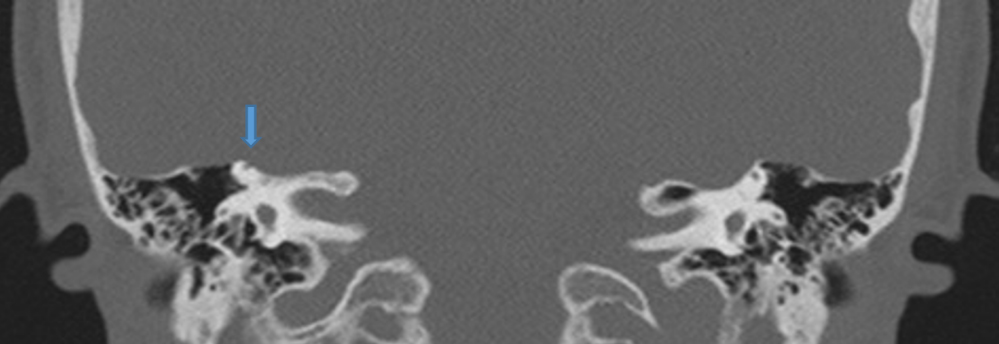

Deiscenza (assenza di osso) della parete del canale semicircolare superiore destro (2022)